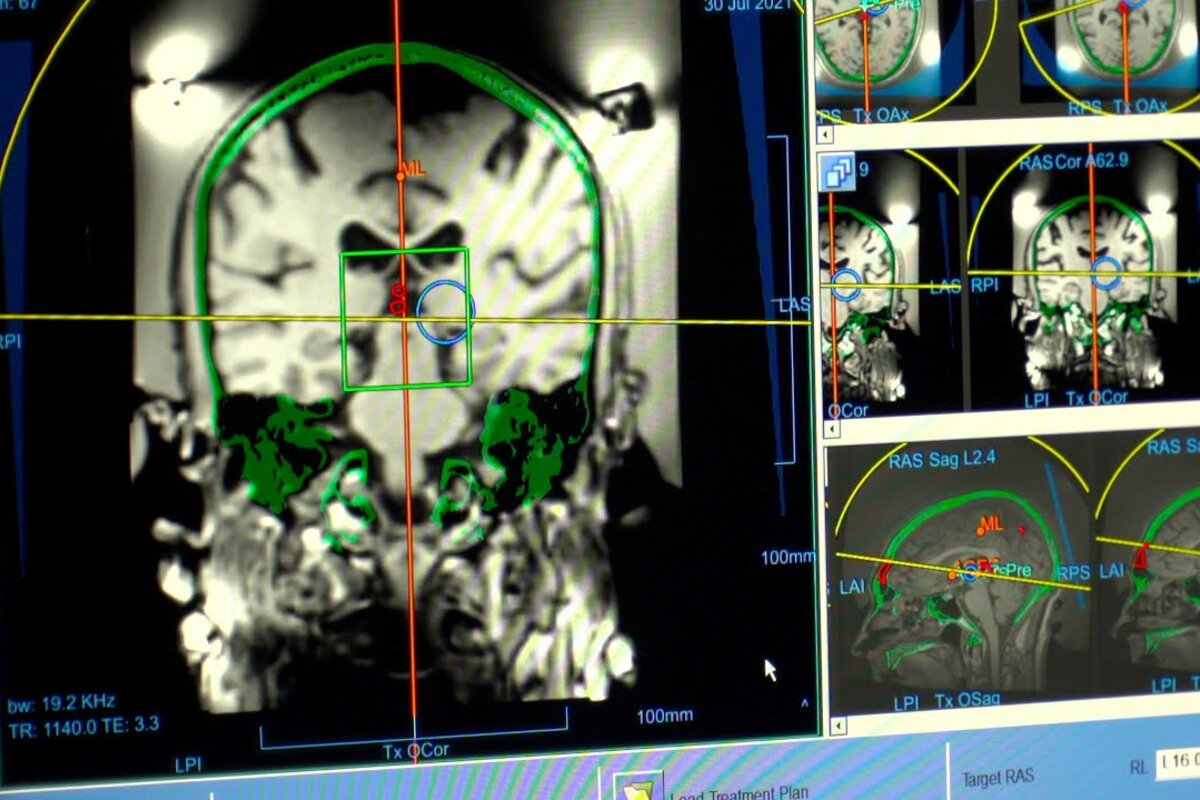

Director, Functional Neurosurgery & Epilepsy Program; Co-Director, Deep Brain Stimulation; Laboratory Director, Cognitive Neurophysiology & Neuromodulation

Asaad's clinical interests include functional neurosurgery for movement disorders and psychiatric disease, traumatic brain injury, and general neurosurgery of the brain and spine.

- Functional Neurosurgery/deep Brain Stimulation